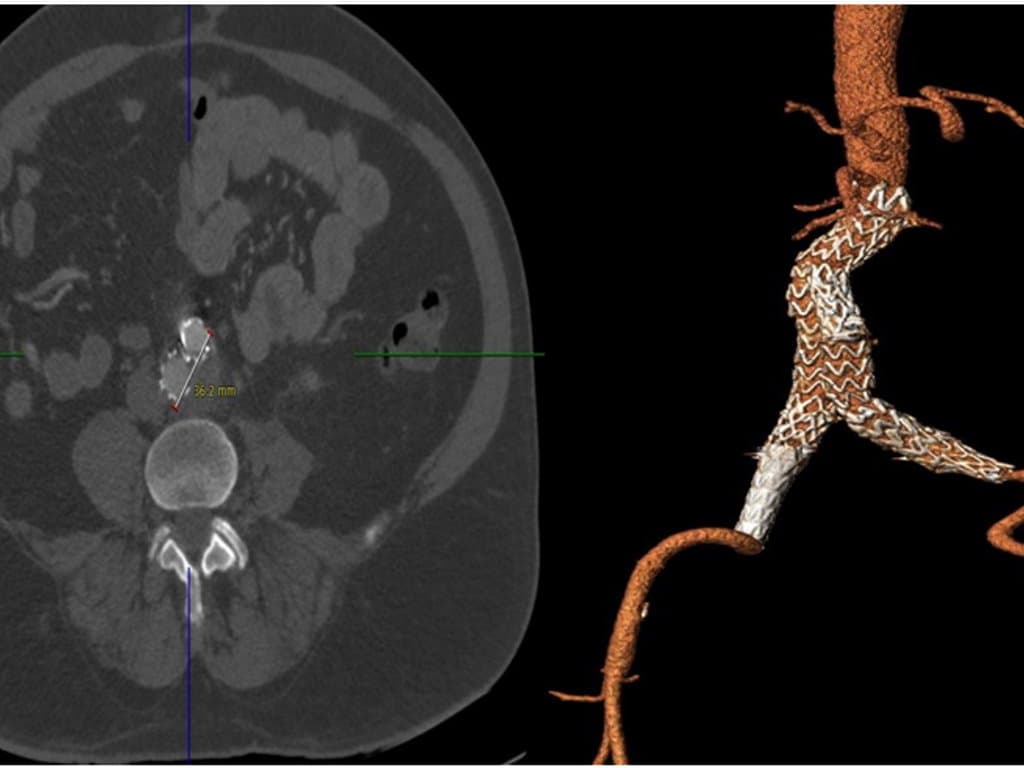

Experts analyzed 529 patients undergoing endovascular aneurysm repair (EVAR) for infrarenal abdominal aortic aneurysm, focusing on DM and metformin's impact on aneurysm sac remodeling. Diabetic patients showed less sac shrinkage at one year and lower overall survival over nine years compared to non-diabetics. Metformin treatment did not significantly alter sac shrinkage outcomes in diabetic patients.